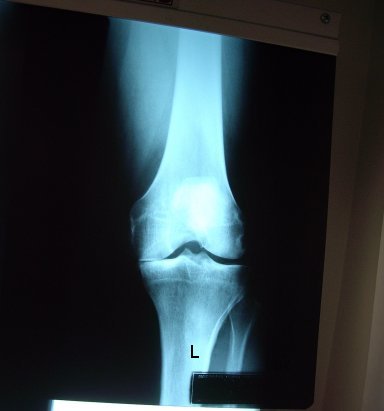

2009_Aug_x-ray

2009_pre-op_x-ray

X-rays and Measurements